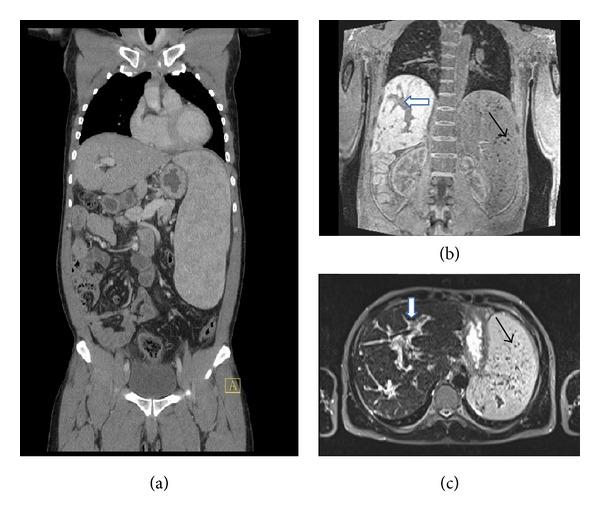

The immune system protects the organism from foreign invaders and foreign substances and is involved in physiological functions that range from tissue repair to neurocognition. However, an excessive or dysregulated immune response can cause immunopathology and disease. A 39-year-old man was affected by severe hepatosplenic schistosomiasis mansoni and by amyotrophic lateral sclerosis. One question that arose was, whether there was a relation between the parasitic and the neurodegenerative disease. IL-17, a proinflammatory cytokine, is produced mainly by T helper-17 CD4 cells, a recently discovered new lineage of effector CD4 T cells. Experimental mouse models of schistosomiasis have shown that IL-17 is a key player in the immunopathology of schistosomiasis. There are also reports that suggest that IL-17 might have an important role in the pathogenesis of amyotrophic lateral sclerosis. It is hypothesized that the factors that might have led to increased IL-17 in the hepatosplenic schistosomiasis mansoni might also have contributed to the development of amyotrophic lateral sclerosis in the described patient. A multitude of environmental factors, including infections, xenobiotic substances, intestinal microbiota, and vitamin D deficiency, that are able to induce a proinflammatory immune response polarization, might favor the development of amyotrophic lateral sclerosis in predisposed individuals.